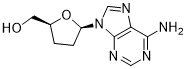

馬鞍山致研生物醫(yī)藥科技有限公司成立于馬鞍山市鄭浦港新區(qū)現(xiàn)代產(chǎn)業(yè)園。公司專(zhuān)注于生物小分子、醫(yī)藥中間體相關(guān)產(chǎn)品的研發(fā)和生產(chǎn),產(chǎn)品主要包括DNA亞磷酰胺單體、RNA亞磷酰胺單體、特殊單體以及按照客戶(hù)要求定制的RNA和DNA,并且公司提供定制合成等方面的研究服...

馬鞍山致研生物醫(yī)藥科技有限公司成立于馬鞍山市鄭浦港新區(qū)現(xiàn)代產(chǎn)業(yè)園。公司專(zhuān)注于生物小分子、醫(yī)藥中間體相關(guān)產(chǎn)品的研發(fā)和生產(chǎn),產(chǎn)品主要包括DNA亞磷酰胺單體、RNA亞磷酰胺單體、特殊單體以及按照客戶(hù)要求定制的RNA和DNA,并且公司提供定制合成等方面的研究服...